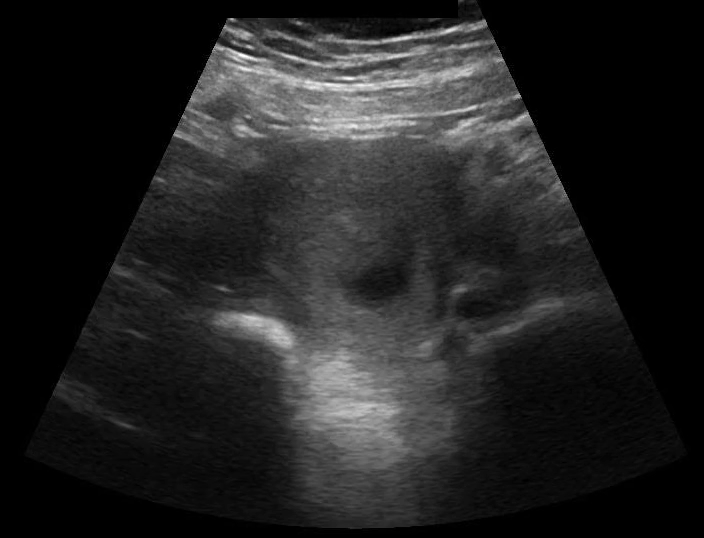

POCUS transabdominal revealed no free fluid in hepatorenal space (image 1), and the uterus without an intrauterine pregnancy (image 2) but with pelvic free fluid (image 3). The left adnexa revealed a gestational sac with a yolk sac (image 4), diagnostic for an ectopic gestation.

Image 2: Transverse view of the pelvis with possible gestational sac without a yolk sac, so no intrauterine pregnancy. At the end of the clip a very concerning left adnexal structure comes into view briefly.